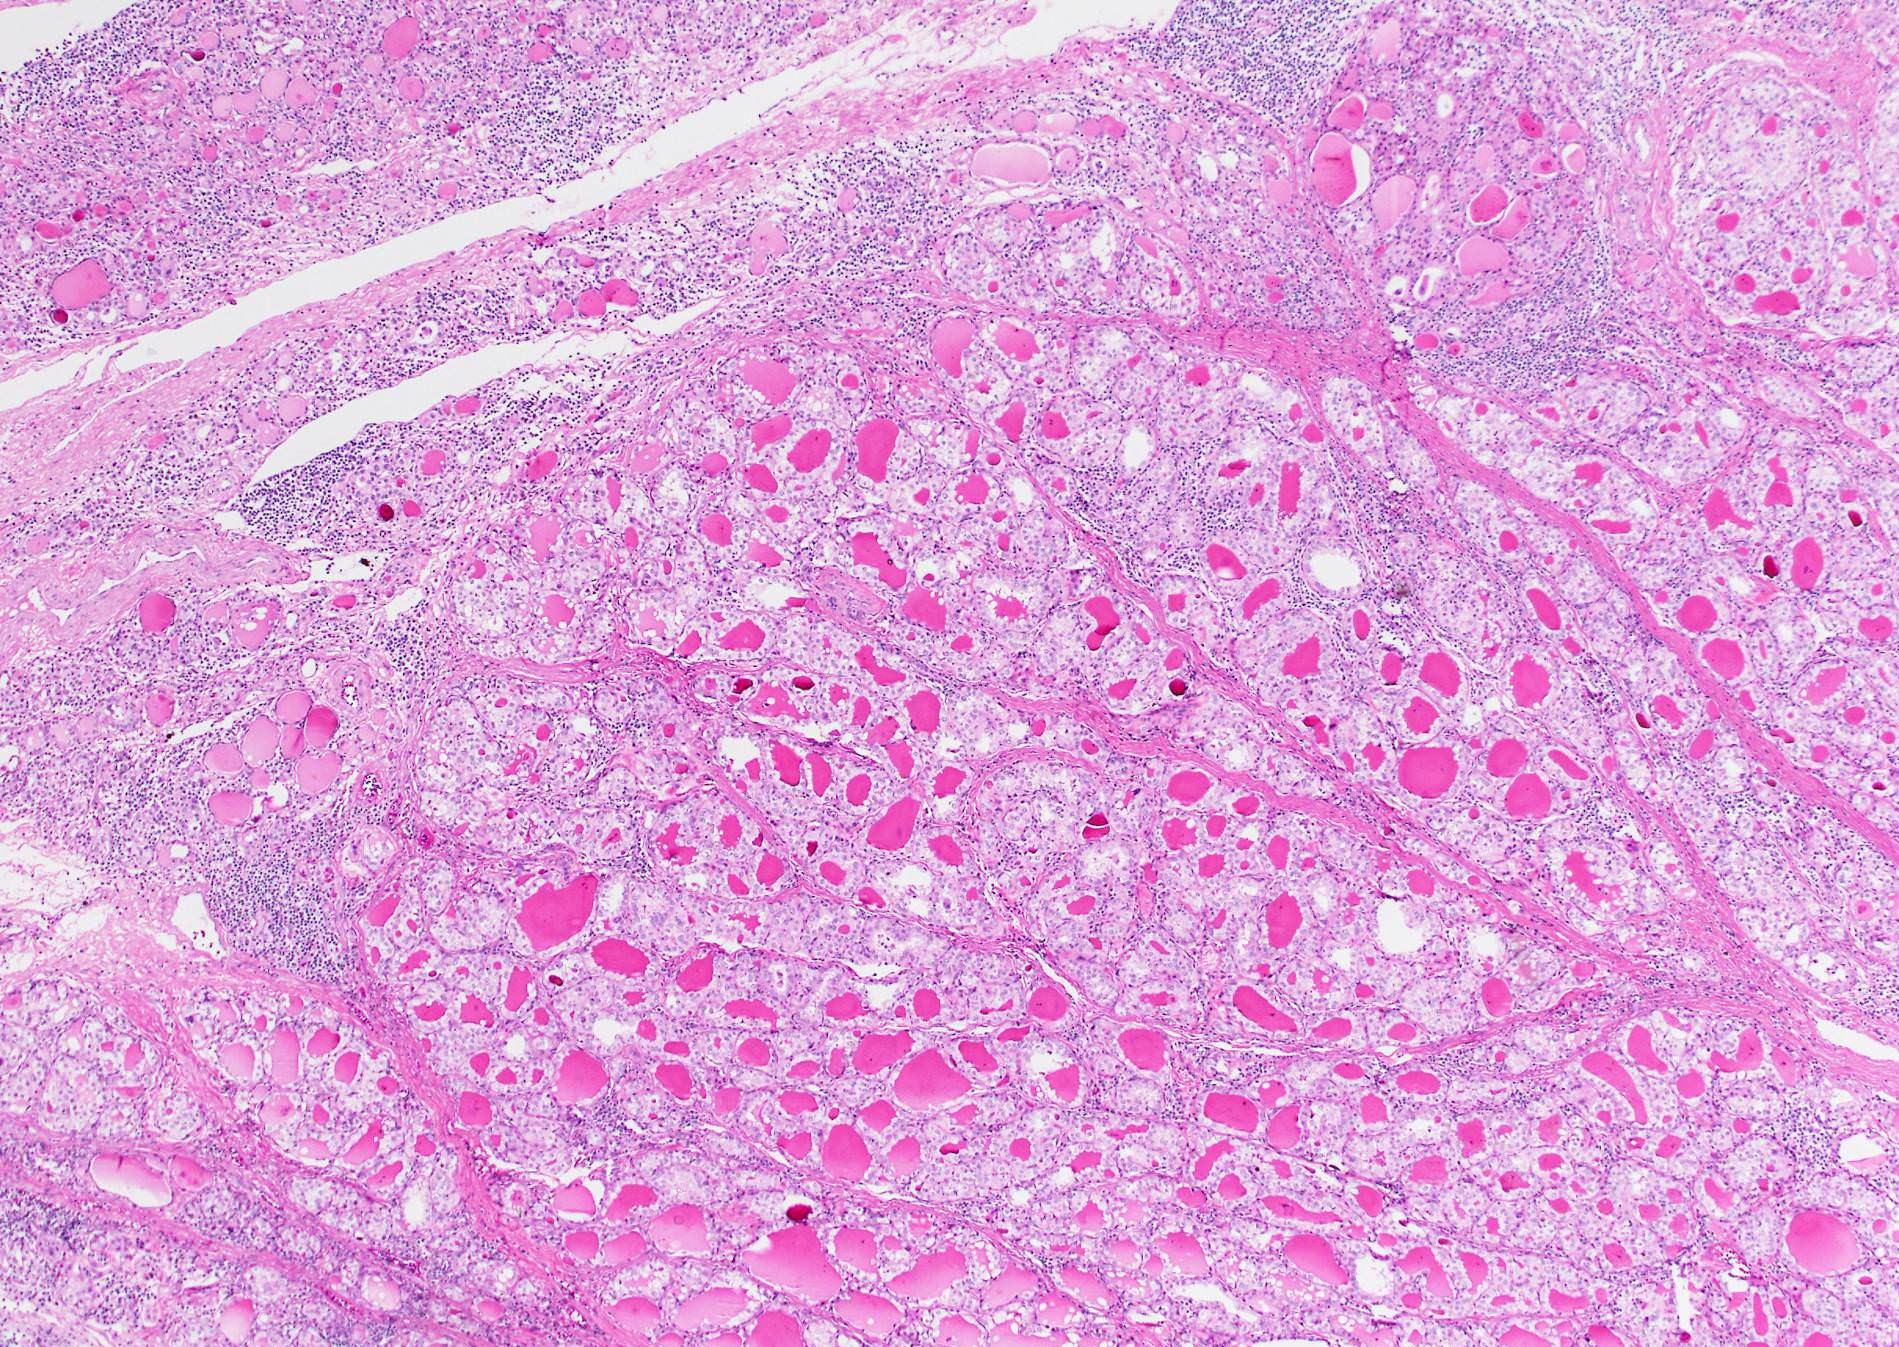

Microscopic (histologic) description

- Architecture: exclusively or nearly exclusively follicular

- True papillae with fibrovascular core are in general absent in follicular variant

- Solid architecture may be present: tumors with mixed follicular and solid architecture should be classified as follicular variant, whereas those with (almost) exclusive solid growth are classified as solid variant

- Infiltrative follicular variant shows infiltrative or multinodular growth

- Sprinkling sign refers to the phenomenon that neoplastic follicles are seen scattered within the background of normal follicles

Microscopic (histologic) images